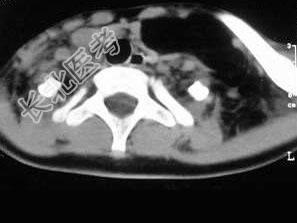

- 单项选择题女,17岁, 发现左侧颈部包块半年余,PE: 病灶质软,境界不清, 无压痛,CT如图所示, 最可能的诊断是 ( )

D、颈部淋巴管瘤